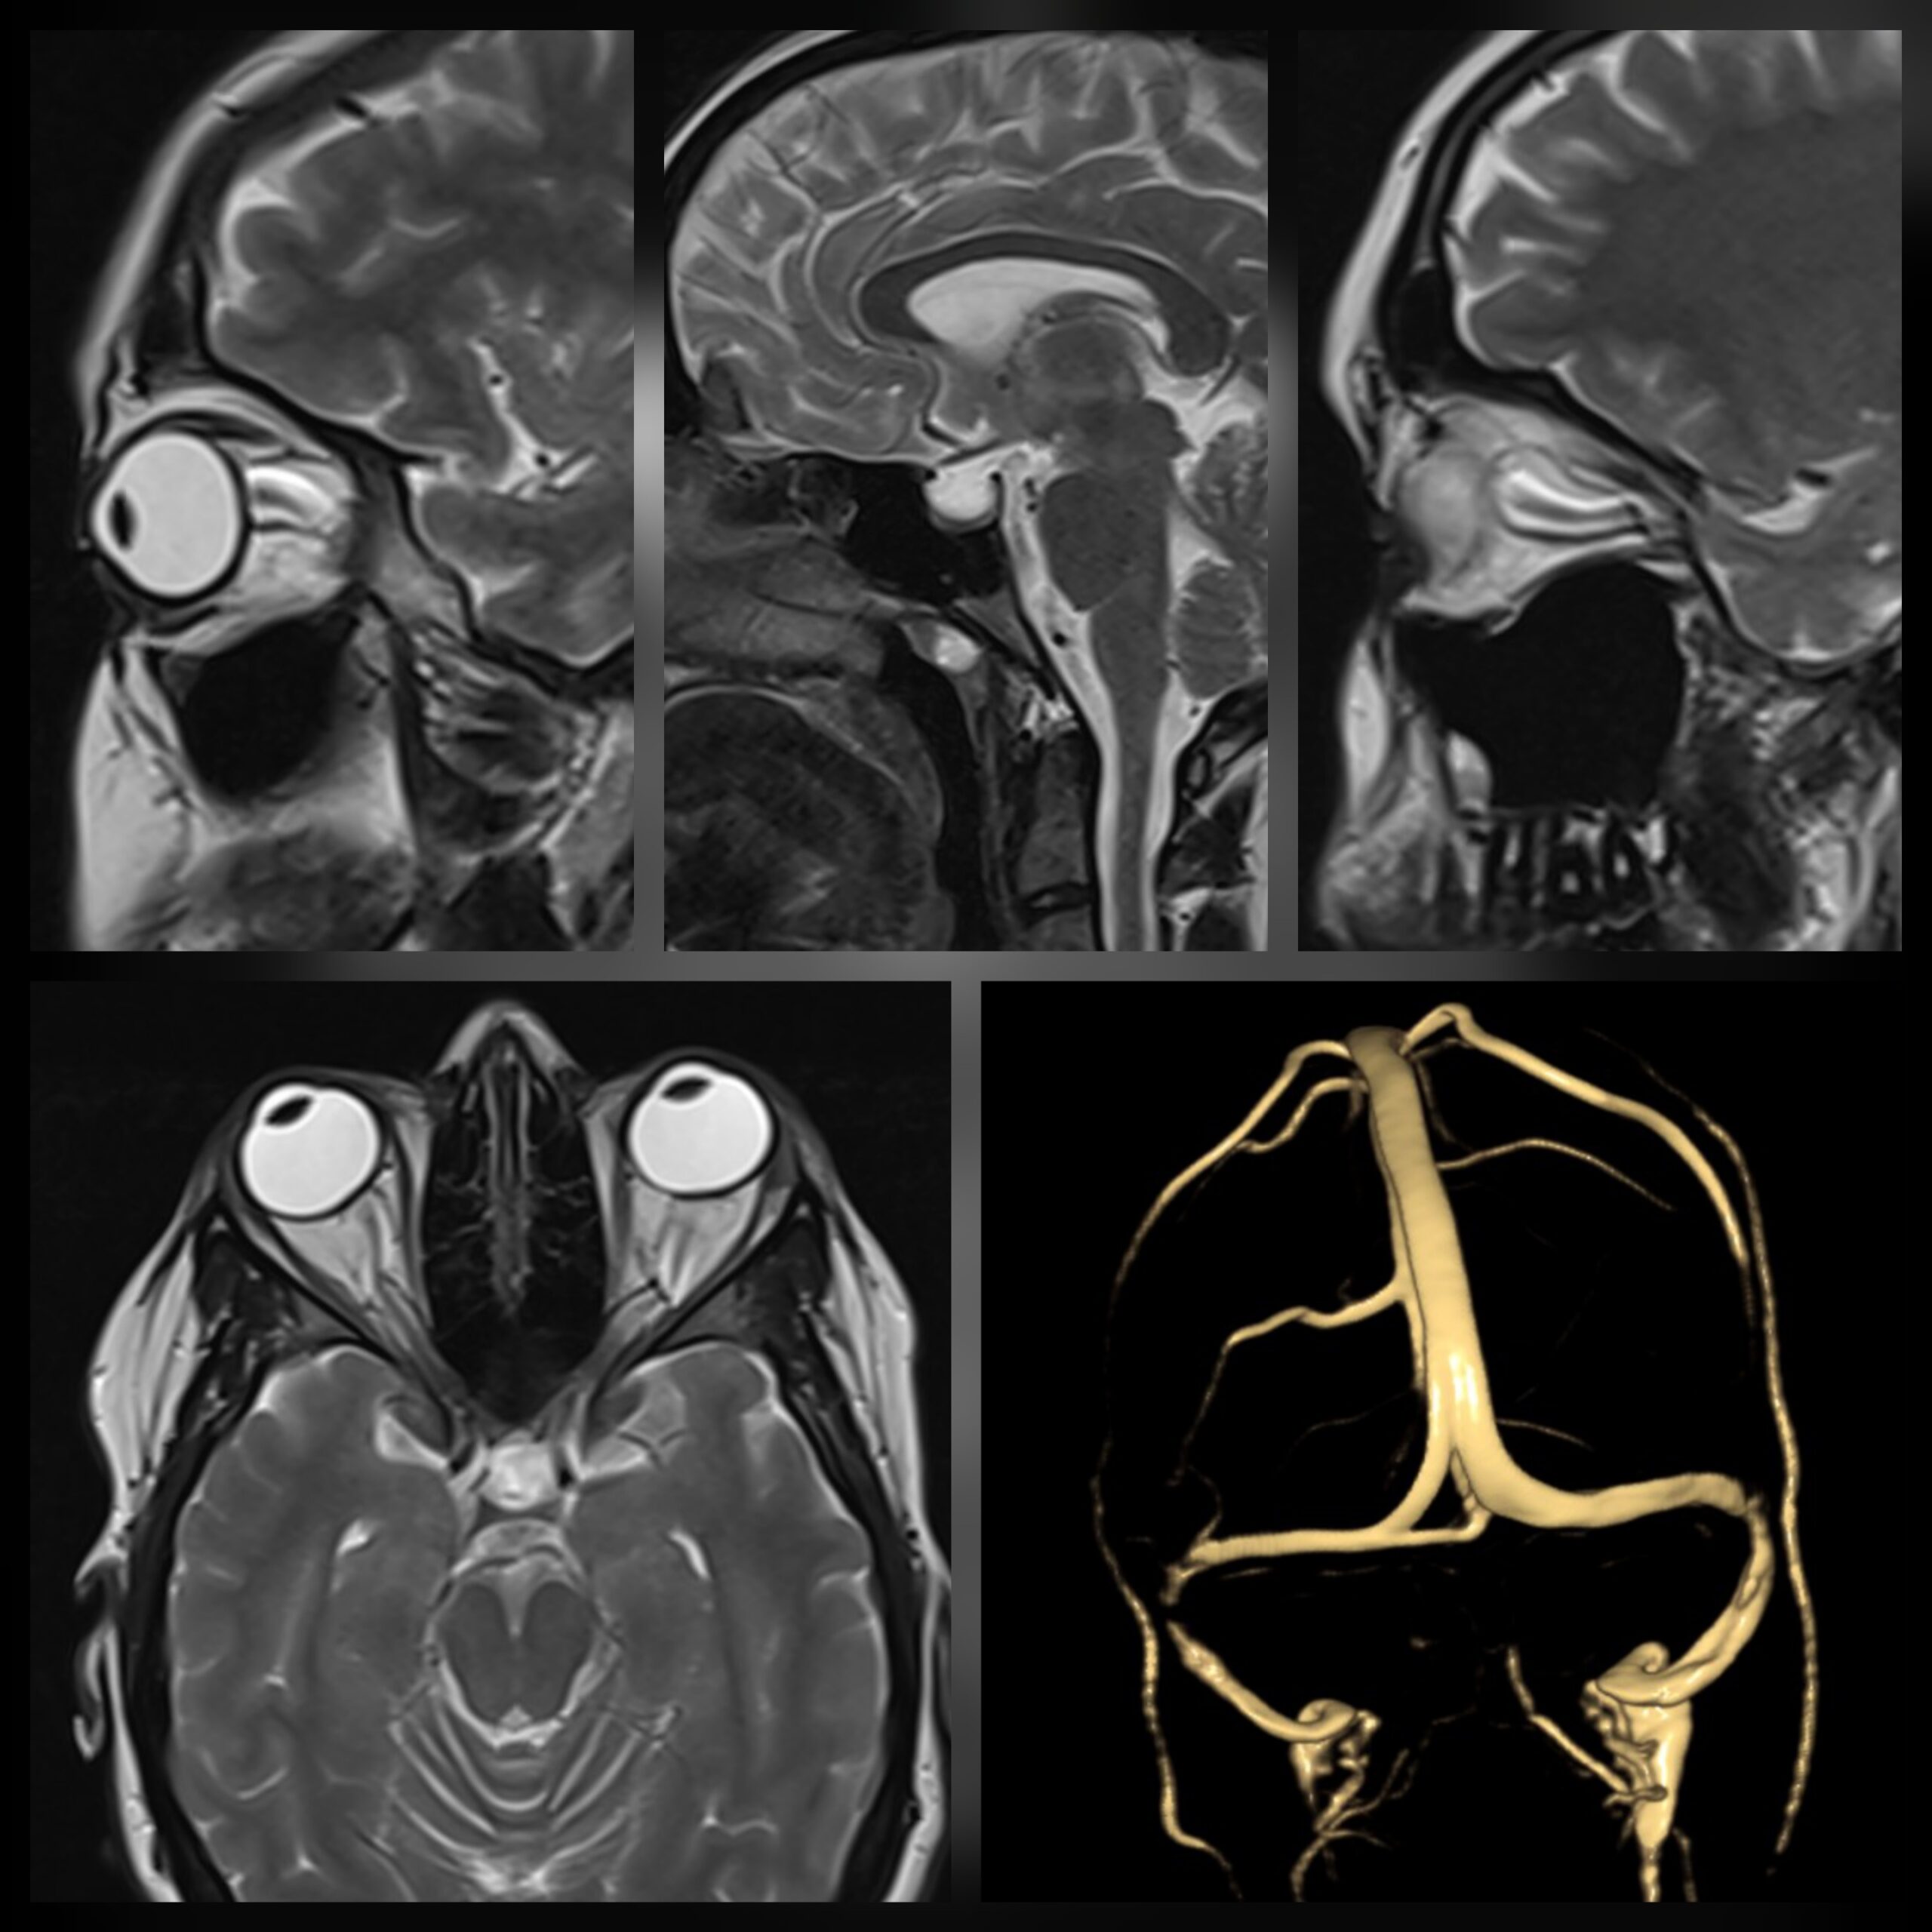

وعلى الرغم من ارتفاع ضغط المخ، إلا أن مسارات السائل النخاعي في هذه الحالات تكون ذات حجم طبيعي وأحياناً أصغر من الطبيعي! وهو ما يظهر بوضوع في أشعة الرنين المغناطيسي على المخ.

– أشعة الرنين المغناطيسي على المخ وأوردة المخ.

وتركيب الصمام من المخ إلى البطن يحتاج إلى أجهزة توجيه جراحية لتوجيه الصمام إلى المكان السليم داخل بطيلنات المخ؛ نظراً لصغر حجم بطبنات المخ في هذه الحالات.